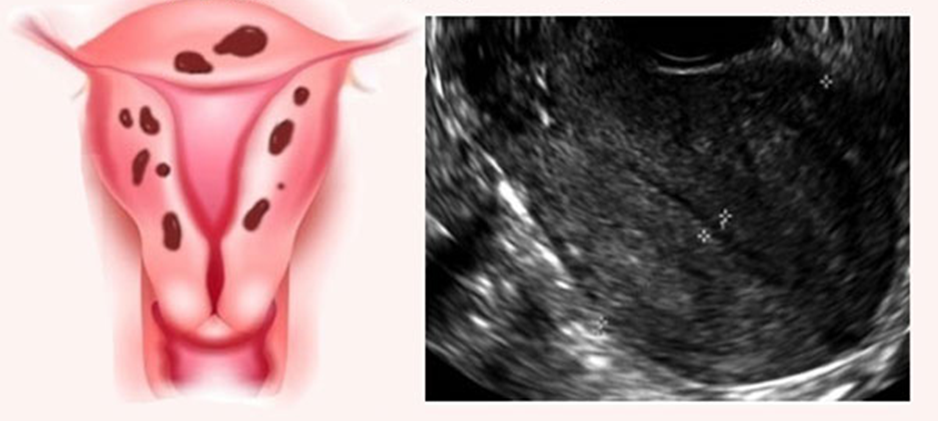

УЗИ и не только

Также необходимо проведение ультразвукового исследования гинекологической сферы, а также ректальное исследование и ректовагинальное исследование, необходимо проведение кольпоскопии, гистероскопии и лапароскопического исследования.

Именно гистероскопическое и лапароскопическое исследования наиболее часто выявляют очаги эндометриоза в области половых органов и в других местах. Эти исследования требуют особых условий для проведения – в том числе и проведения наркоза, и кроме того, они являются параллельно с диагностическим, еще и лечебным свойством.

Основные показания к проведению гистероскопиии и лапароскопического исследования – это проявления хронической тазовой боли, которая длится более полугода. При таких исследованиях у женщин выявляются увеличение матки пости у 70% пациенток, особенно при аденомиозе и примерно у 25-30% женщин с проявлениями наружного эндометриоза. Обычно выявляются признаки умеренного увеличения в области матки.